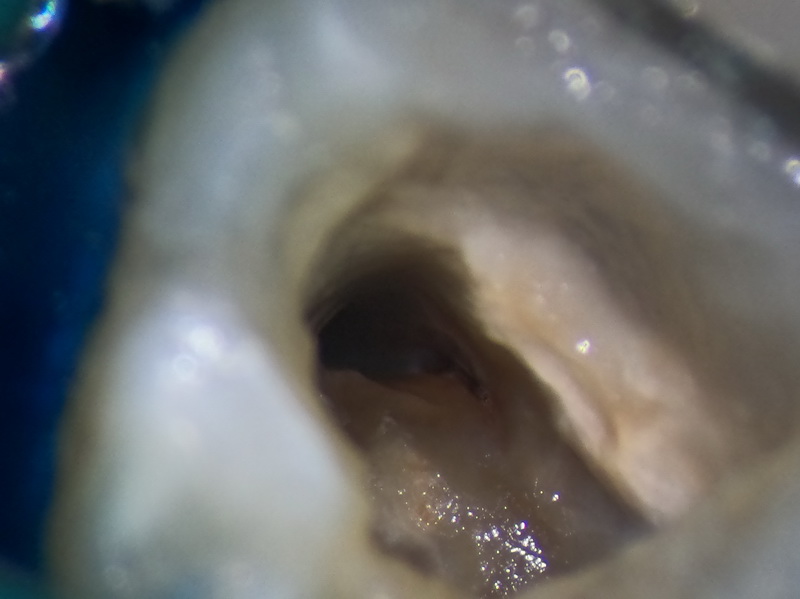

Під місцевою анестезією проведено ізоляція зуба, видалення старої пломби з карієсом під нею, відбудова зруйнованої стінки, розпломбування кореневих каналів з використанням операційного мікроскопу, обробка каналів по сучасним протоколам, та пломбування кореневих каналів біокерамічним цементом з відновленням зуба композитним матеріалом.

Контроль пломбування на рентгенівському знімку показав високу якість пломбування, що дає змогу зробити хірургічне втручання у гайморову пазуху.